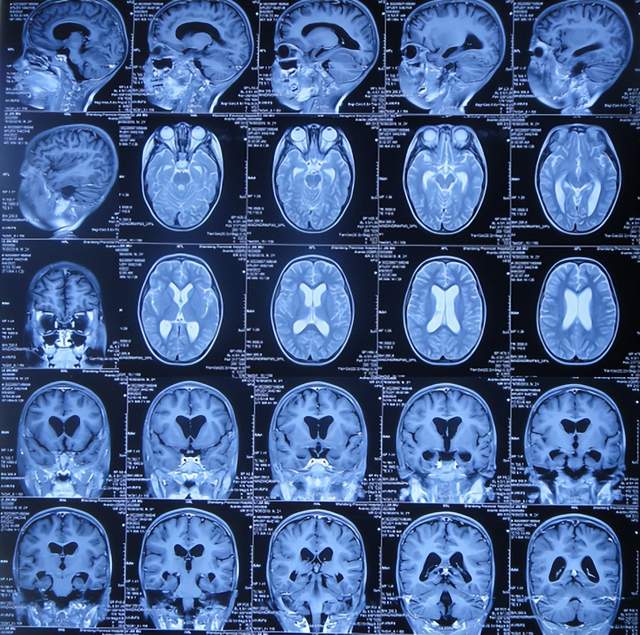

第3家医院治疗16天即2022年6月9日,不但依然发热,而且查头颅CT示脑室稍扩张(图-3)。

图-3:2022年6月9日头颅核磁

但该院治疗12天即2022年6月29日,复查头颅核磁脑室扩张进一步加重(图-6)。

图-6:2022年6月29日头颅核磁

入院当天查头颅CT示脑室扩张(图-8)。

图-8:2022年7月1日入院时头颅CT